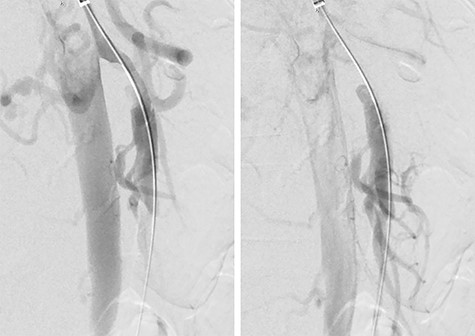

She was admitted and maintained on bowel rest and heparin infusion. Given persistent pain after 2 days of non-operative management, an abdominal arteriogram was performed through a left axillary artery cutdown. The dissection was identified 1.5 cm distal to the origin of the SMA (Fig. 2). Intravascular ultrasound was used to determine diameters and landing zones for stent placement (Fig. 3). The dissection was initially treated with a 6 mm × 40 mm self-expanding stent followed by post-dilation with 4 mm × 40 mm and 6 mm × 40 mm balloons. A 5 mm × 19 mm stent graft was deployed proximally with small overlap and ~3-mm extension into the aorta. Completion angiogram showed <10% residual stenosis (Fig. 4). As the right external iliac artery dissection was small and asymptomatic, no intervention was performed.

Post-stenting angiogram of the SMA demonstrating preservation of the middle colic artery as well as the distal branches of the SMA.